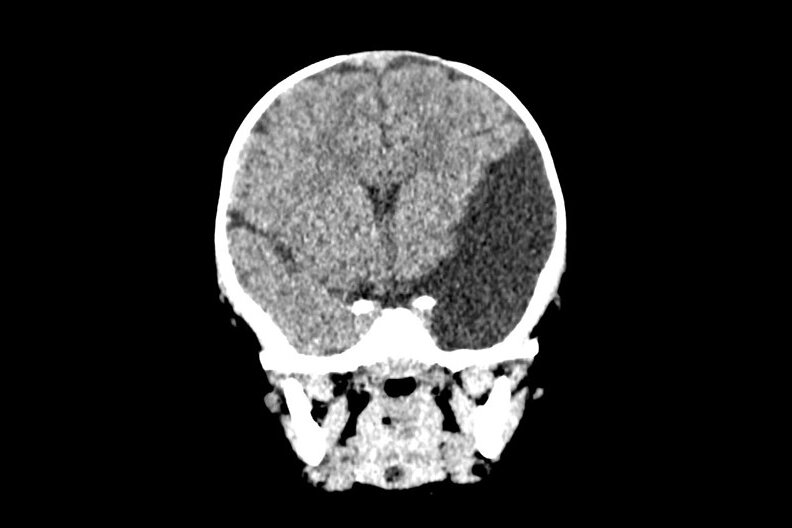

Неудачное падение героя нашей статьи повлекло за собой длительную головную боль, вялость, тошноту в течение нескольких дней. Родители ребенка обратились в стационар. Младенцу было проведено специализированное обследование — спиральная компьютерная томография головы. По результатам которой докторами был поставлен диагноз «сложный врожденный порок развития головного мозга: Арахноидальная киста левого полушария больших размеров, вызывающая выраженное сдавление височной и лобной долей».

Фото из архива ДГКБ им. З.А. Башляевой

Описанное образование головного мозга сопряжено с высоким риском разрыва стенок кисты и резких ухудшением состояния ребенка, вплоть до неблагоприятного исхода даже при незначительных травмах головы.

Проведена контрольная томография головного мозга. Арахноидальная киста сократилась в 2 раза, головной мозг хорошо расправляется.